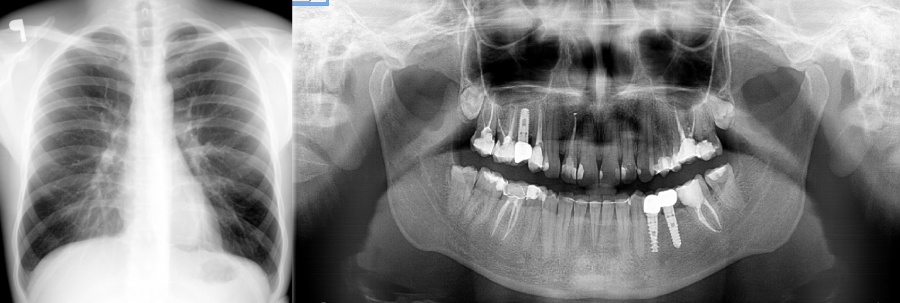

Dobry stomatolog często wykorzystuje RTG pantomograficzne lub tomografię zębów do pierwszej konsultacji.

Kompleksowa konsultacja stanu uzębienia obejmuje ocenę stanu koron zębów widocznych w badaniu bezpośrednim, ale równie ważne są szyjki i korzenie zębów, które są ukryte pod dziąsłami oraz błona śluzowa jamy ustnej.

diagnostykę radiologiczną (rtg zębów, zdjęcia pantomograficzne, tomografia zębów - RTG 3D)

Nic prostszego! Udaj się do stomatologa i poproś o badanie! Dobre kliniki stomatologiczne oferują bezpłatne konsultacje. Profesjonalna usługa w tym zakresie powinna obejmować prześwietlenie zębów! Znajduje tu zastosowanie złota zasada w medycynie: "korzyści muszą przewyższać ryzyko". W przypadku nowoczesnej aparatury cyfrowej korzyści zawsze wygrywają. Dawka promieniowania jest najniższe z możliwych, a wczesne wykrycie toczącego się poddziąsłowo procesu chorobowego pozwoli uniknąć poważnych konsekwencji! W praktyce pozornie zdrowe uzębienie często ujawnia niebezpieczne zmiany w okolicy wierzchołka korzenia zębowego! Niestety alarmujące objawy najczęściej pojawiają się zbyt późno! Oprócz utraty zdrowia narażamy się na rosnące koszty leczenia. Najgorszym z możliwych scenariuszy jest sytuacja, kiedy proces chorobowy zniszczył kość w stopniu uniemożliwiającym podjęcie leczenia kanałowego, protetycznego, implantologicznego lub nawet zagrażającym pęknięciem kości żuchwy w wyniku osłabienia kości przez np. rosnącą torbiel.

Wybierz lekarza, który prowadzi proces diagnostyczno-terapeutyczny w oparciu najnowsze wytyczne i technologie! Innymi słowy wybierz nowe, precyzyjne i lepsze techniki zamiast "sprawdzonych"metod polegających jedynie na wizualnej ocenie koron zębów! Dopiero diagnostyka radiologiczna daje możliwość pełnej oceny stanu jamy ustnej. Medycyna nie stoi w miejscu... W innym wypadku nadal wypełnienia stomatologiczne/plomby opierały by się na amalgamatach. Pozostało po nich tylko wspomnienie!